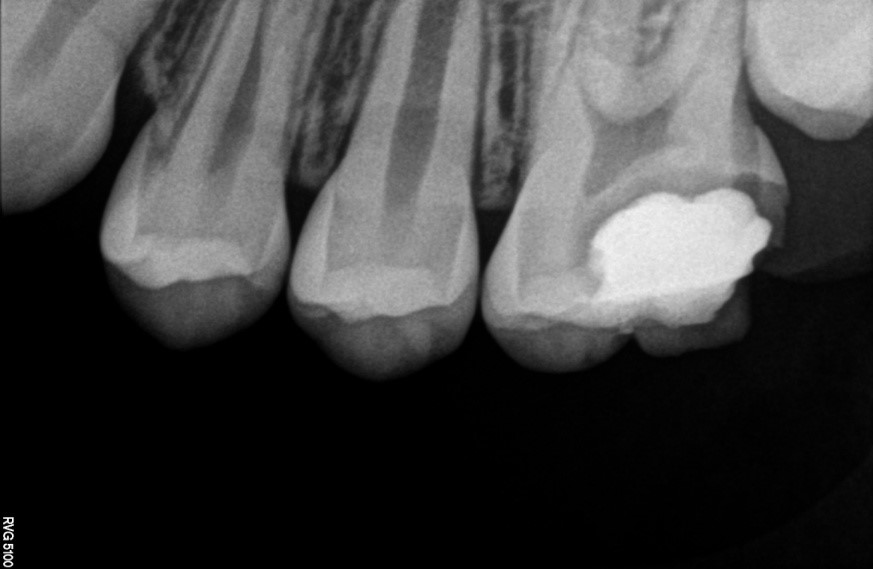

Caso clínico premolar